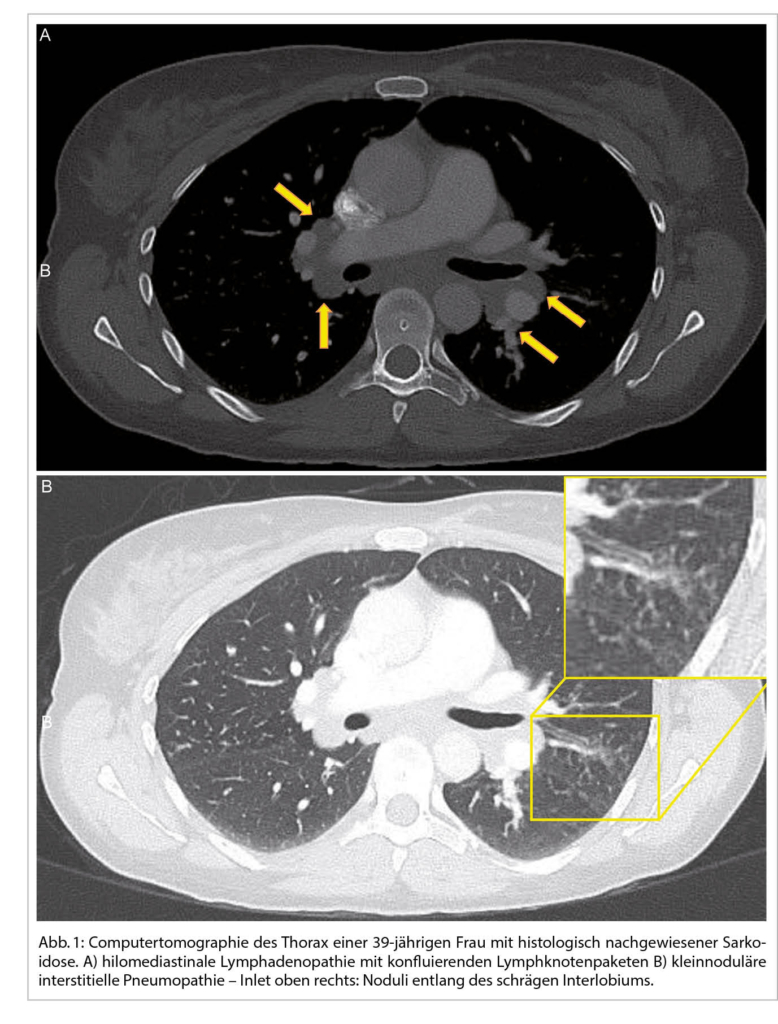

Eine typische Verlaufsform einer akuten Sarkoidose ist das Löfgren-Syndrom. Dieses zeichnet sich durch ein gleichzeitiges akutes Auftreten von Fieber, Erythema nodosum mit schmerzhaften, knotigen Schwellungen der Unterschenkel, einer meist die OSG-betreffenden Oligoarthritis und einer symmetrischen bihilären Lymphadenopathie aus. In den meisten Fällen liegt allerdings eine chronische Verlaufsform vor. Etwa 85% der Patienten haben einen intrathorakalen Befall – Lymphadenopathie mit oder ohne Befall des Lungenparenchyms. Die klinische Präsentation umfasst Husten, Dyspnoe und Thoraxschmerzen, die von Müdigkeit, Gewichtsverlust, Fieber und Unwohlsein begleitet sein können. Extrapulmonale Manifestationen treten bei der chronischen Form der Sarkoidose in bis zu 30% der Patienten auf (3). Grundsätzlich können alle Organe betroffen sein.

Bei einer typischen Präsentation eines Löfgren-Syndromes kann auf eine bioptische Diagnosesicherung verzichtet werden. Im Normalfall wird die Diagnose durch den Nachweis von epitheloidzelligen Granulomen und Auschluss einer anderen granulomatösen Erkrankung gestellt. So muss im Ausschlussverfahren das Vorliegen einer infektiösen Erkankung (vor allem Tuberkulose, Pilzinfekte), einer «sarkoid-like» Reaktion assoziiert mit malignen Erkrankungen, sowie unter weiteren einer Berylliose ausgeschlossen werden. Da in den meisten Fällen die Lunge betroffen ist, kommt der Bronchoskopie als sicheres und minimal-invasives Verfahren eine wichtige Rolle zu. Bei der Bronchoskopie kann eine Gewebeprobe asserviert und eine broncho-alveoläre Lavage durchgeführt werden. Bei einem extrapulmonalen Befall entscheidet häufig die Zugänglichkeit einer Gewebeprobe über die Durchführung des geeigneten Diagnoseverfahrens. Zudem ist initial ein Organscreening indiziert, um eine subklinische Organbeteiligung erfassen zu können. Hierfür wird eine ophtalmologische Untersuchung, ein Abdomenultraschall und eine kardiologische Beurteilung mit EKG, transthorakaler Echokardiographie und 24 h-EKG empfohlen. Die Labordiagnostik umfasst Differentialblutbild, Leber- (AP, γGT) und Nieren- (Kreatinin, GFR) Tests, Serumkalzium sowie eine Bestimmung der angiotensin-converting enzyme (ACE) und löslichen IL-2-Rezeptor alpha (sIL-2Rα). Dazu folgt eine Urinanalyse mit Kalziumspiegel und Sediment sowie eine fraktionierte Kalzium-Ausscheidung. Die radiologische Klassifikation nach John Scadding ist immer noch in Gebrauch und hat einen prognostischen Wert. Eine funktionelle Untersuchung der Lunge (Spirometrie, Bodyplethysmographie und CO-Diffusion) und eine hochauflösende Computertomographie (HRCT) sind die bevorzugten Methoden zur Beurteilung der Lungenbeteiligung und ihres Schweregrads (1). Eine Lungensarkoidose kann sowohl zu restriktiver, wie auch obstruktiver oder gemischter Ventilationsstörung führen.